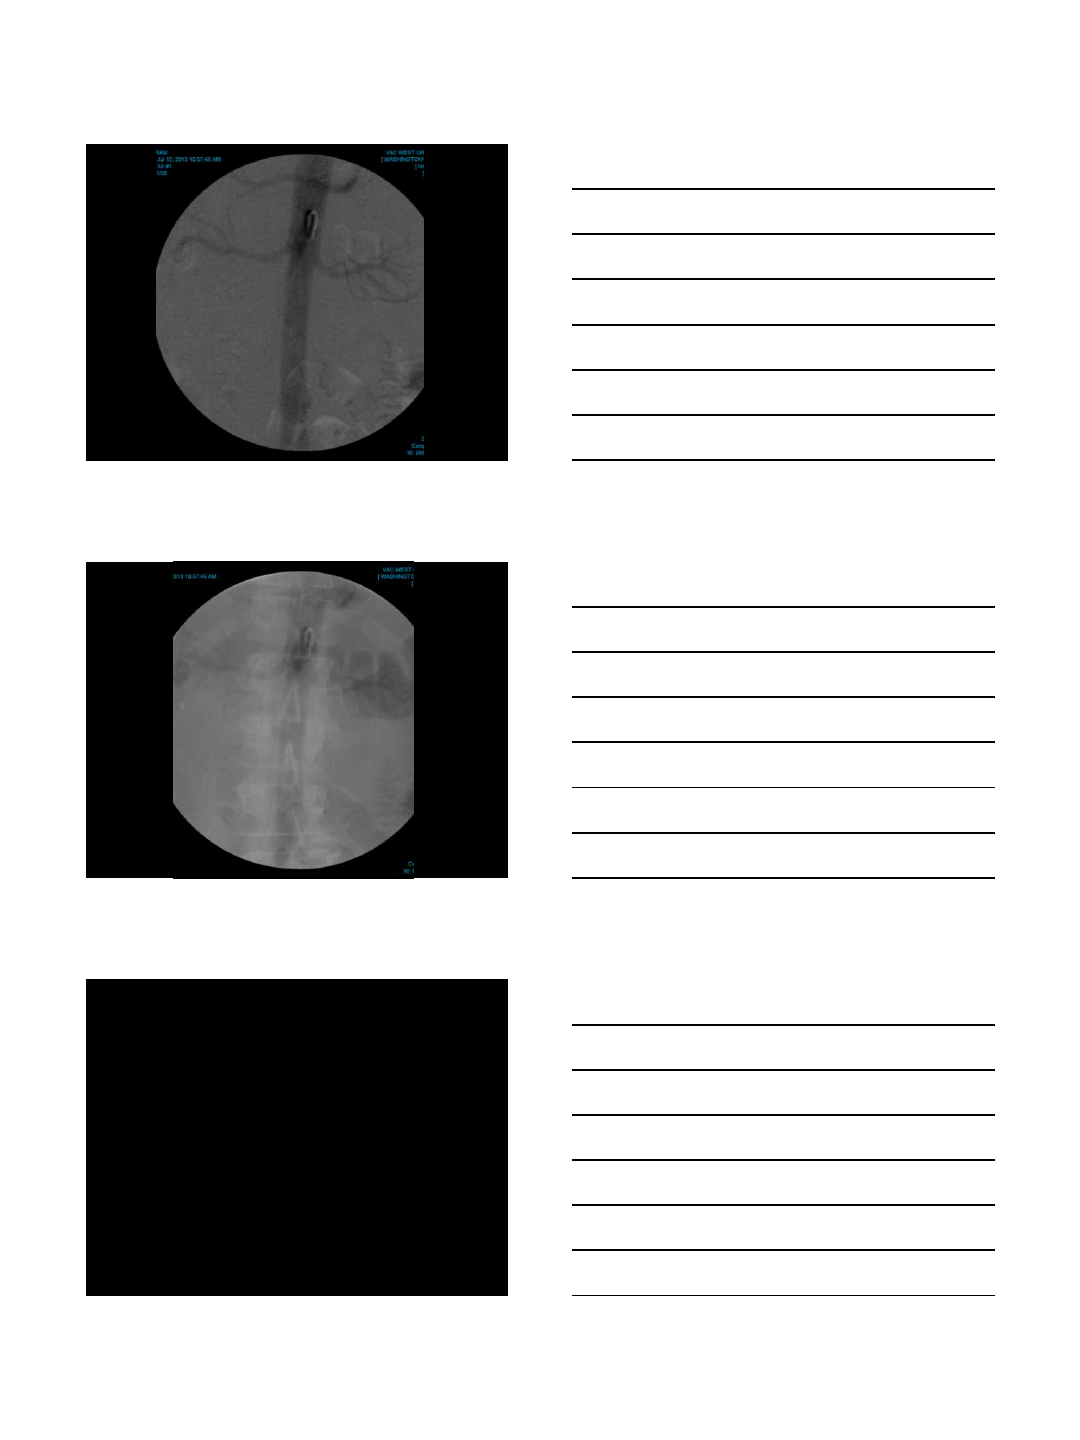

ANEURYSM REPAIR

Case Presentation

•78 year old man with severe atherosclerotic

disease, chronic renal failure with a stable

serum creatinine at 2.5 mg/dL and a large

iliac artery aneurysm

•Needs aneurysm repair but it is desirable to

CO2 arteriogram and embolization

•Iliac aneurysm coiling with CO2

•AAA stent-graft using CO2 & IVUS

•Total contrast used: 30 cc

•Renal function unchanged